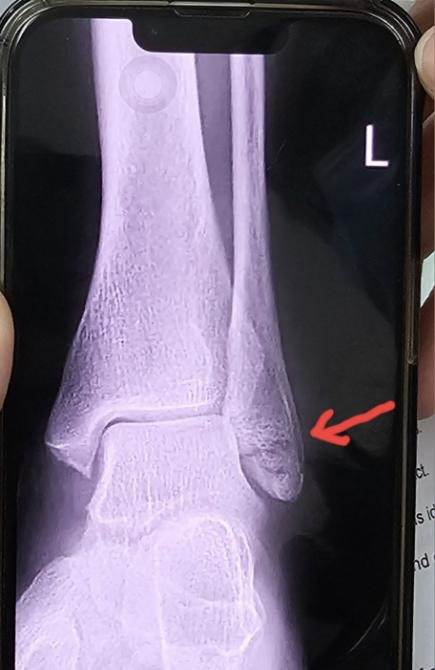

X-rays confirmed it: a complete spiral fracture of the fibula. After some waiting, the orthopedic doctor arrived and placed a splint on my ankle for support. He explained that a cast couldn’t be applied yet because the swelling from the trauma still needed to subside. A follow-up consult and evaluation were scheduled seven days later.